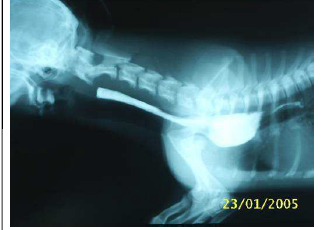

Observe esta radiografia contrastada:

Fonte: http://vetcordis.com/artigos/artigo_2.htm

Esta imagem é típica de uma afecção comum em cães. Há uma sombra menos radiopaca abaixo do contraste que serve de orientação. O que representa a porção contrastada?